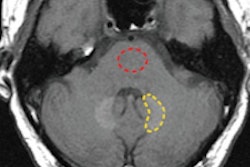

MR imaging was performed using a Signa 1.5-tesla system (GE Healthcare) with dedicated phased-array coils. MRI scans were enhanced with an intravenous bolus of Gd-DOTA at a rate of 0.2 mL/kg. The smallest amount of Gd-DOTA per child ranged from 0.6 mL in a 3-day-old newborn male to 4 mL in an 18-month-old female. The median injection of Gd-DOTA was 2 mL, followed by a saline flush of the same amount.

The study also rated MR image quality with Gd-DOTA on a five-point scale, ranging from excellent to poor. Gd-DOTA-enhanced MR images were also rated for their diagnostic contributions from definitely normal to probably abnormal and how the scans affected a child's treatment, if at all.

In addition, image quality was rated as "excellent/good" for Gd-DOTA-enhanced MRI in 102 children (98%). Diagnostic contribution was also assessed as optimal (definitely abnormal/normal diagnosis) in 101 cases (97%). The use of Gd-DOTA MRI also confirmed the correct choice of initial treatment in 50 children (48%).